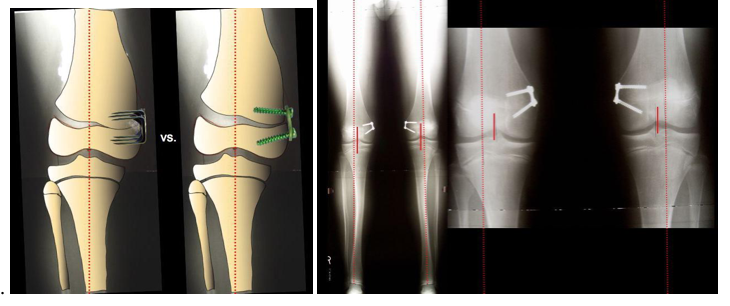

Gối vẹo ngoài quá mức ở trẻ đến 7 tuổi là sinh lý và không phải là bệnh lý. Vấn đề là trẻ em trên 8 tuổi có gối vẹo ngoài từ mức vừa đến nặng (trên 12 độ). Bệnh nhi thường than phiền đau ở đùi và / hoặc bắp chân và dễ mỏi, trẻ đi với hai đầu gối cọ xát với nhau, hai bàn chân tách ra và một chân đong đưa xung quanh chân kia. Thông thường, cha mẹ lo lắng với dáng đi này. Do không thẳng trục và tăng góc Q làm cho xương bánh chè dễ bán trật ra ngoài, khớp bánh chè đùi không vững. Bàn chân thường tựa vào mặt trong (sụp xuống) do các lực chịu trong lượng bất thường ở cổ và bàn chân.

Hình ảnh học:

X quang cho phép phân biệt gối vẹo ngoài do phát triển hay bệnh lý.

Ở tuổi vị thành niên với gối vẹo ngoài nặng gây lệch trục rõ rệt, có chỉ định điều chỉnh bằng phẫu thuật. Có hai phương pháp phẫu thuật: làm dính nửa bản sụn tăng trưởng (bên trong) đầu dưới xương đùi và/hoặc đầu trên xương chày và phẫu thuật cắt chỉnh xương (với xương trưởng thành).